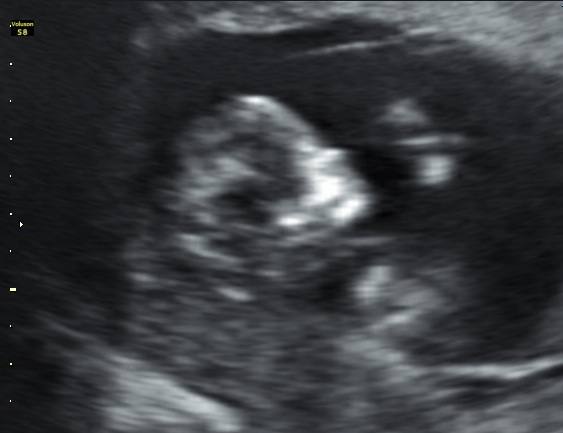

Hi everybody's here is a twelve week ultrasound pic, any guesses going by shape of the foreheads? Both are same baby!